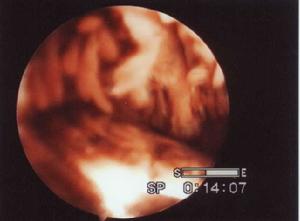

膝關節創傷常可引起關節內血腫,多由於關節內骨折、或韌帶、滑膜等軟組織、手術等引起。亦有其他原因如壞血病、血友病、絨毛結節滑膜炎等,統稱為自發性關節內積血。

膝關節內血腫,因有纖維蛋白酶作用很少凝固、機化大都保持流動狀態。積血中的紅細胞溢出到滑膜細胞間隙,並滯留於該處,以及滑膜下組織內,其他則被滑膜細胞吞噬、碎裂而轉化為多中心或單中心的蝸狀帶膜小體和含鐵小體,遺留在關節內的積血如未被吸除則因含鐵血黃素沉著而導致關節周圍纖維化。

其臨床特點是膝關節創傷後,短時間內迅速腫脹,因關節內張力急速增加以及紅細胞破壞後的產物,對滑膜的刺激,可引起輕度局部疼痛。體溫與局部溫度均會增高。當診斷不肯定時,則應穿刺確診。